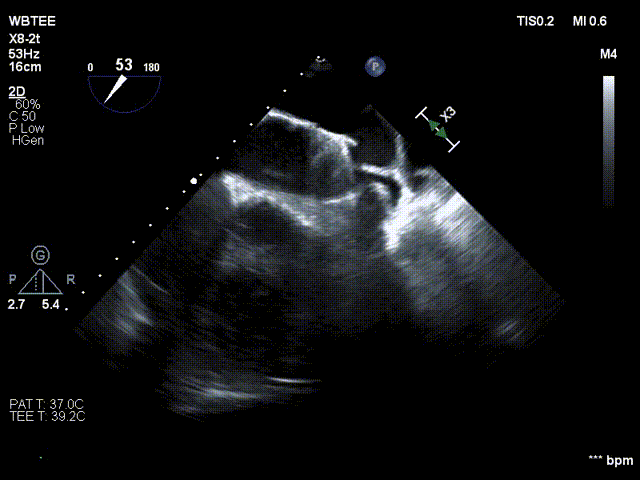

术前行经食道超声评估

原发性二尖瓣反流,反流程度4+;二尖瓣瓣口面积4.15cm²,平均跨瓣压差5mmHg,二尖瓣前叶(A2)长度23.35mm,二尖瓣后叶长度(P2)长度13.2mm;左室射血分数67%。患者手术风险高,操作难度大,经心脏瓣膜团队多次充分讨论评估后,决定行经导管二尖瓣缘对缘修复治疗。

术前MDT策略:从解剖结构来看二尖瓣后叶脱垂伴连枷涉及整个2区,累及3区和1区,宽度15mm左右,且连枷高度甩起高度有7-8mm,可见长达10.4mm的飘样回声,术前策略预计使用两个二尖瓣夹,较小的二尖瓣口面积和较高平均跨瓣压差,是一次高难度的挑战。